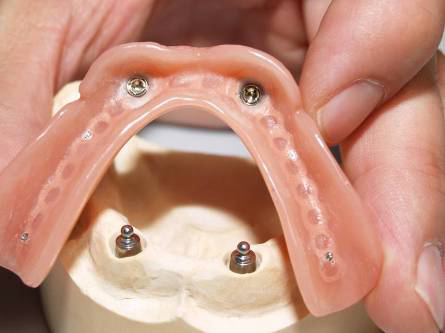

Bezzubá čelist je hlavní indikací pro ošetření pomocí implantátů. Zejména celkové zubní náhrady v dolní čelisti mají velice nízkou stabilitu a držení díky velkému úbytku kosti.

S pomocí zubních implantátů můžeme díky různým kotevním systémům (třmeny, kulové hlavy, Locatory) zajistit stabilitu a držení protézy nebo při použití většího počtu implantátů zhotovit pevné náhrady – můstky nalepené nebo našroubované na pevno na implantáty.